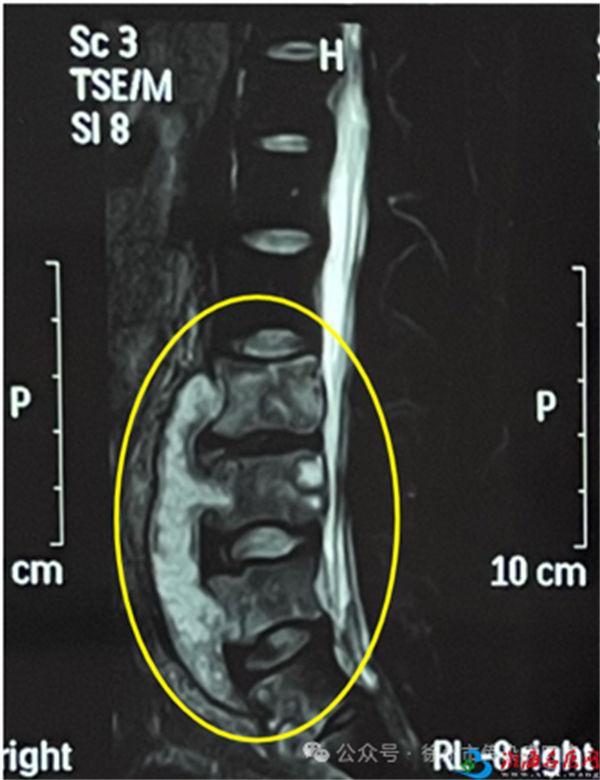

患者就医时有无肺结核病史,影像学检查X线、CT、MRI可以观察到骨骼的异常改变,如骨质破坏、骨髓炎、骨膜反应等。血液检查γ干扰素释放试验、结核菌素(PPD)有助于诊断。明确的诊断需要在病灶部位组织活检或脓肿抽吸,通过病理学检查、病原学检查确诊。